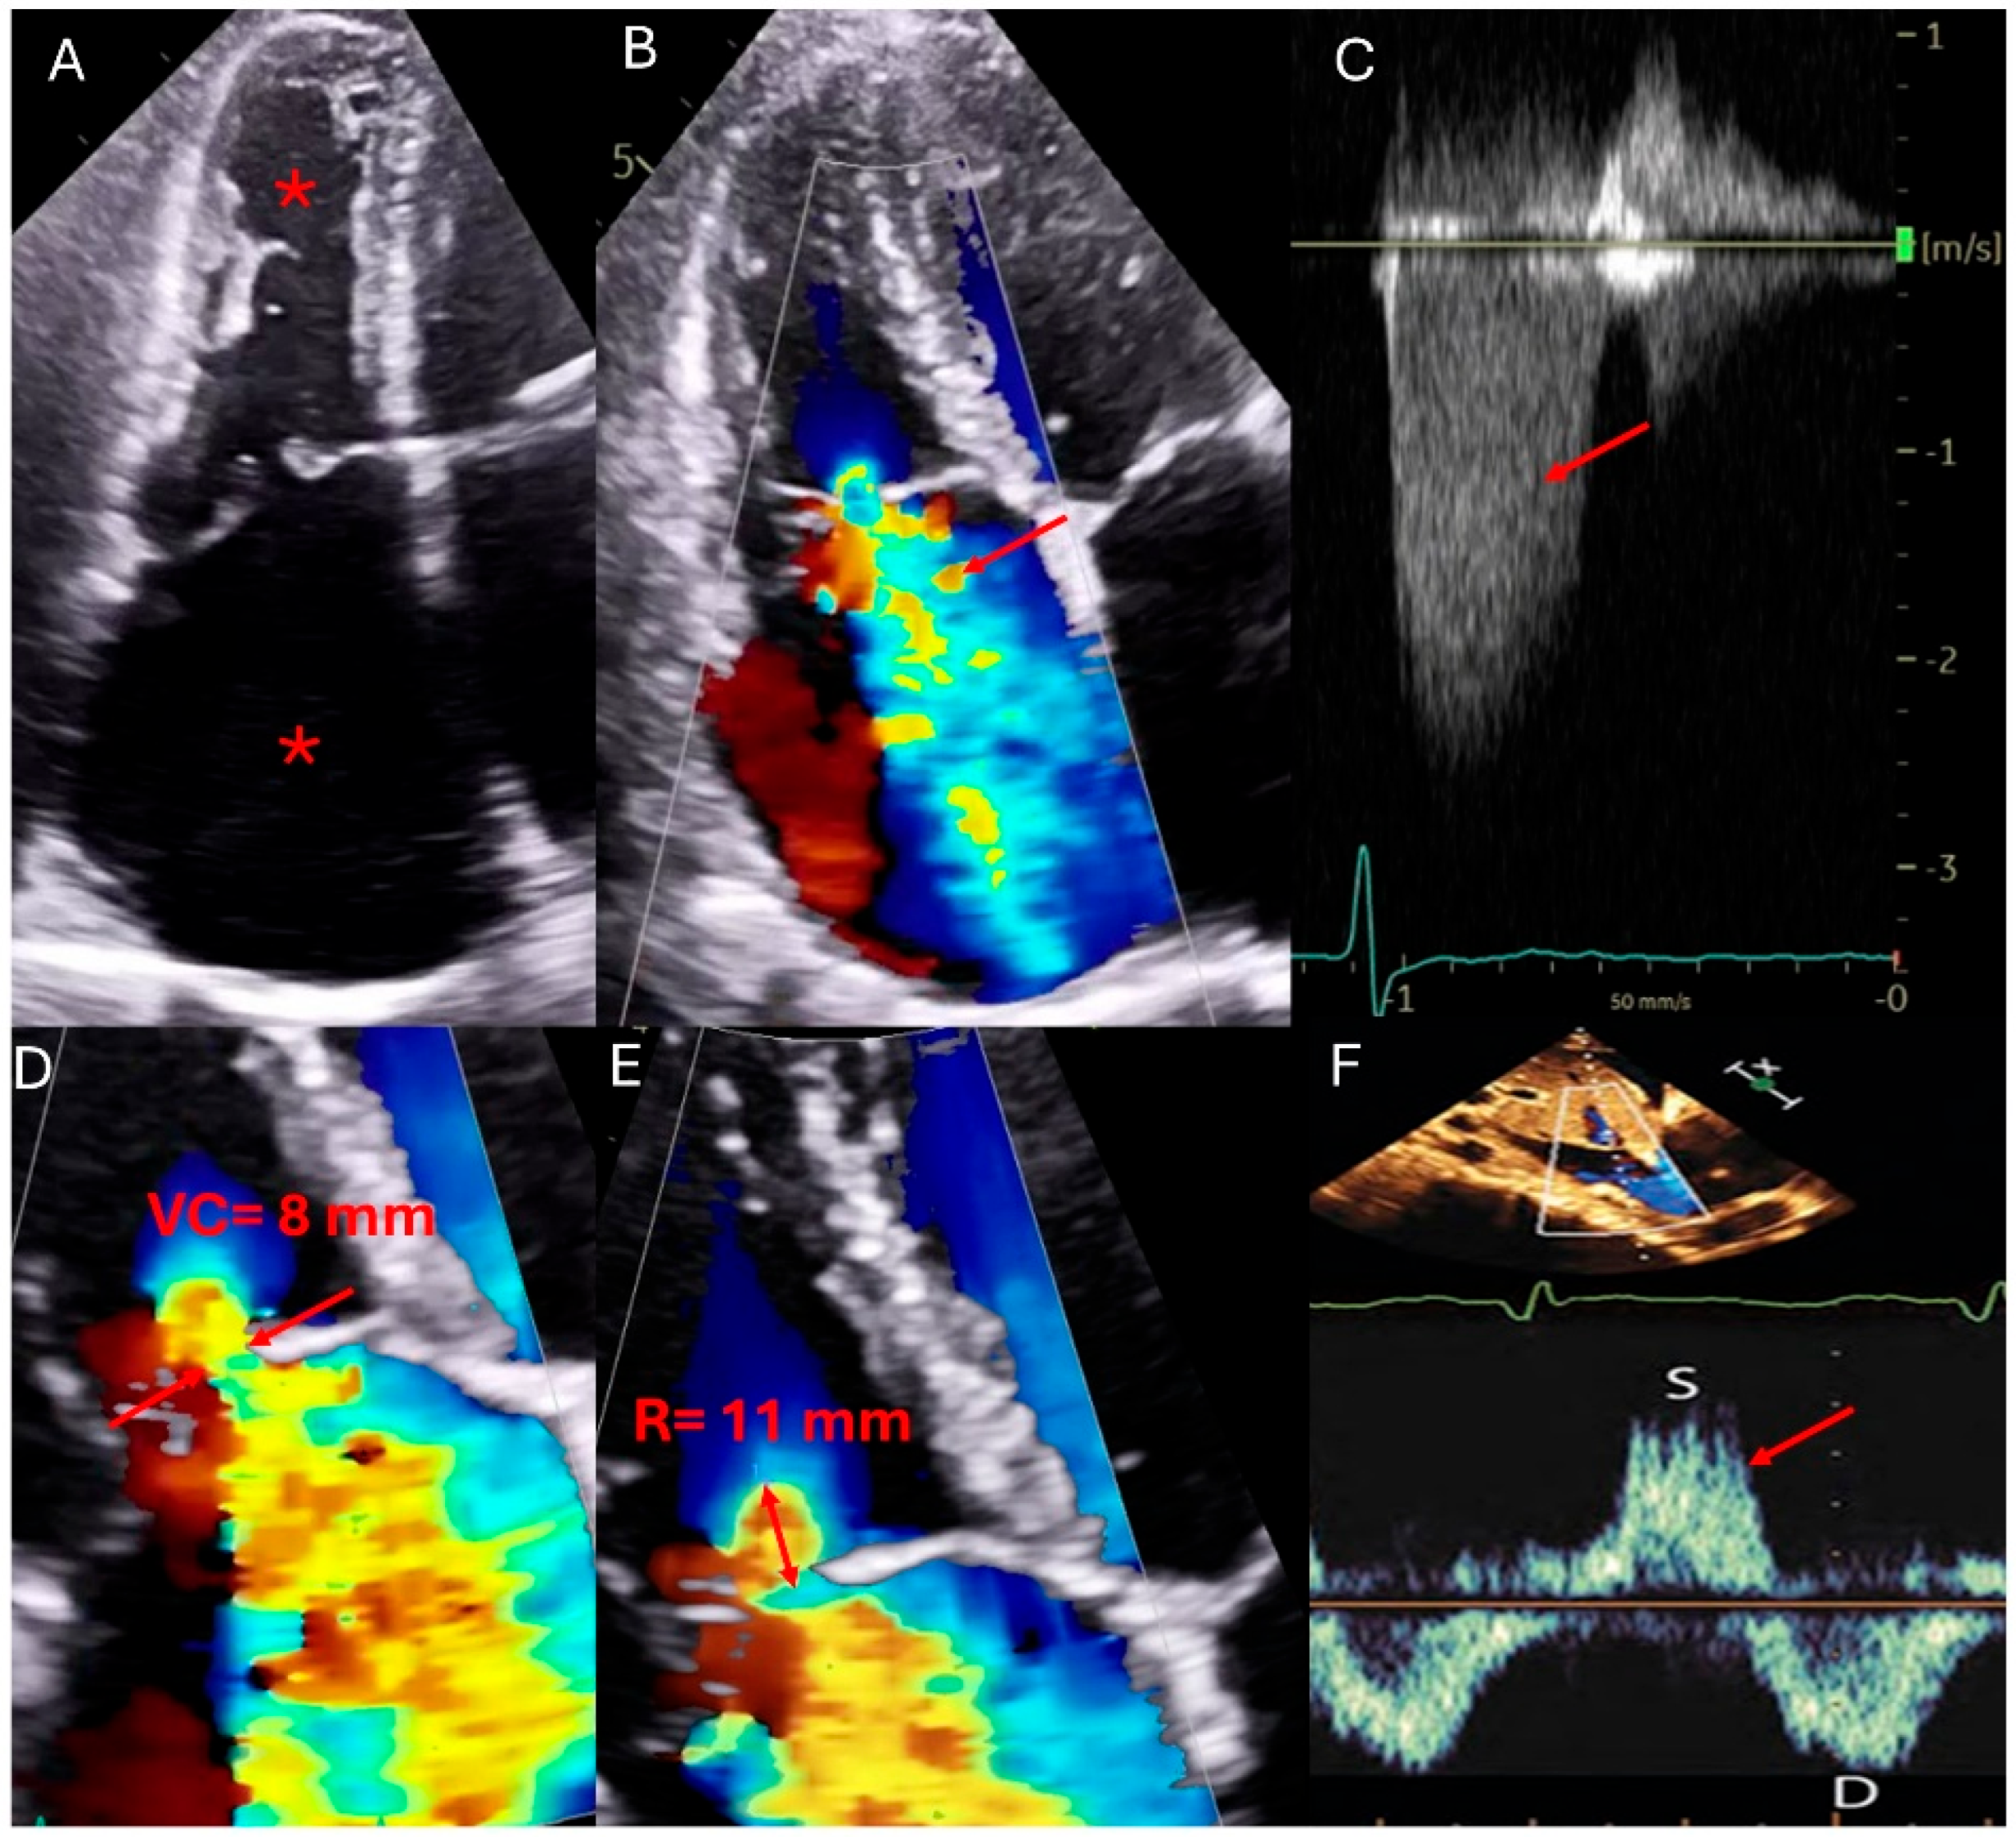

Figure 1—Echocardiographic qualitative and quantitative measures of TR.

Qualitative and quantitative parameters of severe tricuspid regurgitation (TR by echocardiography). (A) Apical four-chamber view showing right atrial (RA) and right ventricular (RV) dilation (asterisks). (B) Color Doppler highlights a large TR jet occupying > 50% of the RA. (C) Continuous-wave Doppler across the tricuspid valve reveals a dense, early peaking spectral Doppler profile (red arrow). (D) Zoomed view of the tricuspid valve shows a vena contracta width exceeding 7 mm (distance between tips of red arrows). (E) Proximal Isovelocity Surface Area (PISA) method demonstrates a large flow convergence zone (radius of 11 mm), with an effective regurgitant orifice area (EROA) ≥ 0.4 cm2. (F) Pulsed-wave Doppler of the hepatic veins shows systolic flow reversal (red arrow), a key marker of severe TR.

In the echocardiographic assessment of TR, various qualitative, semi-quantitative, and quantitative parameters are used to classify the severity into mild, moderate, and severe categories. Qualitatively, TV morphology can range from mildly abnormal leaflets, such as mild rheumatic thickening or limited prolapse in mild cases, to severe valve lesions like flail leaflets, ruptured papillary muscles, severe retraction, or large perforations in severe TR [22]. Interventricular septal motion and characteristics of the flow convergence zone and the TR jet’s continuous wave (CW) Doppler signal vary significantly, from minimal abnormalities in mild cases to extensive changes in severe TR (Figure 1). Semi-quantitatively, the inferior vena cava (IVC) diameter, color flow jet area, vena contracta width, and proximal iso-velocity surface area (PISA) radius provide insights into the regurgitant flow, with all parameters increasing significantly as the severity progresses [22].

Quantitative measures such as the effective regurgitant orifice area (EROA) and regurgitant volume by PISA and 3D techniques further delineate the severity, with values escalating from less than 20 mm2 and under 30 mL in mild cases to more than 40 mm2 and over 75 mL in severe TR [22]. Hepatic vein flow and tricuspid inflow measurements complement these findings, helping to confirm the severity as indicated by systolic dominance in mild cases and systolic flow reversal in severe TR. These comprehensive assessments not only enhance the understanding of the pathological impact of TR but also guide clinical decision-making regarding the timing and type of therapeutic intervention needed [23,26] (Table 2).